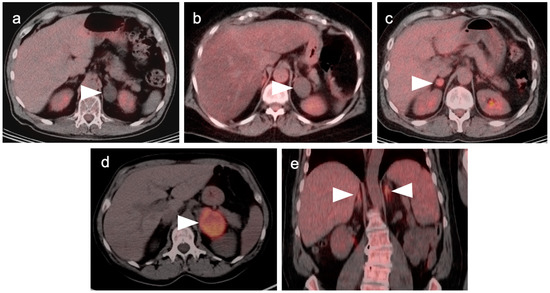

7. Adrenal Cancer